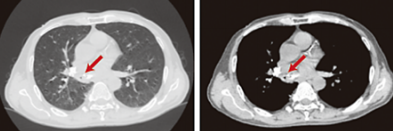

• 胸部CT:纵隔、肺门区见多处高密度钙化灶,右中间支气管明显狭窄,右肺下叶还有黏液栓、阻塞性肺炎表现。

图1:患者胸部CT

• 支气管镜:右中间支气管内侧壁向外凸起,黏膜充血肿胀,管腔显著变窄,腔内有脓性分泌物。